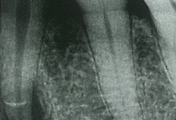

ledge가 형성되는 이유는 다음과 같습니다. Ni-Ti file을 만드는 재료는 금속입니다. 아무리 유연성 있는 재료라 한들 금속은 기본적으로 직선의 형태를 띱니다. 그런데 대부분의 근관은 만곡을 가지고 있습니다. 따라서 file이 휘어지며 유연하게 근관을 따라가지 못하게 되면 ledge가 형성됩니다. 아무래도 근관 내 만곡이 심할수록 file이 이 만곡을 따라가지 못해 ledge가 발생할 가능성이 높아집니다. 그리고 이렇게 근관 내벽에 한 번 file의 흔적이 생기면, 다음번 file 적용 시에도 같은 위치에 반복해서 닿게 됩니다. 처음 남은 흔적은 크지 않지만 반복해서 같은 부위에 닿게 된다면 흔적이 점차 커지고, 이것이 ledge가 됩니다.

이렇게 상부를 충분히 제거했는데도 만곡이 심하다고 느껴질 수 있습니다. 이럴 때에는 보다 유연한 Ni-Ti file을 사용해야 합니다. 조금 더 유연한 file을 선택하는 기준은 너비가 작은 file을 사용하는 것입니다. 즉, 한 단계 작은 Ni-Ti file을 사용하면 기존보다 file의 유연성이 증가하고, 만곡을 따라가는 전진하는 것이 조금 더 수월해집니다. 이때 한 단계 작은 Ni-Ti file이 없다면 작은 크기의 hand file을 이용해서 근관 전체에 걸쳐 부드러운 filing을 시행해줍니다. 최대한 손을 이용하여 근관 확대에 공을 들일 필요가 있습니다. 만곡이 심한 경우라면 hand file의 끝부분을 미리 조금 구부린 뒤에 사용할 수도 있습니다. 이때 방사선 사진을 참고하면 좋습니다. 이렇게 근관 내부를 성형하고 나면 근관의 만곡도가 조금 줄어드는 효과를 볼 수 있습니다.

또 다른 ledge 예방법으로는 같은 Ni-Ti file을 여러번 사용하지 않는 것이 있습니다. 기본적으로 각 제조사에서는 한 개의 file 당 8번에서 10번 정도의 사용만을 권장합니다. 이 횟수를 측정하기 위해 나온 rubber도 있고, 펜으로 표시하는 술자들도 있습니다. 또 file을 한 번 사용할 때마다 file 보관함을 옮기면서 사용 횟수를 기록할 수도 있습니다. 이렇게 기존에 Ni-Ti file의 사용 횟수를 제한해두는 것이 좋습니다. 또한 방사선 사진을 보며 미리 만곡의 크기를 예상하여, 어려울 것으로 예상되는 신경치료에서는 새로운 Ni-Ti file을 사용하는 것도 좋은 방법입니다.

위와 같이 갖은 노력을 했음에도 불구하고 ledge가 발생할 수 있습니다. 이런 경우 #10번 보다 작은 hand K-file을 사용하여 기존의 길을 우회(bypass)해야 합니다. 이때 K-file을 미리 원하는 각도로 구부려놓는 것이 필요합니다. 그래야 다시 같은 자리에 ledge를 형성하지 않고 원하는 길을 따라갈 수 있습니다. 그리고 이러한 시도가 성공했다면 한 file 단계 당 100번씩은 filing 한다고 생각해야 합니다. 이렇게 해서 다시 순차적으로 #25번 K-file까지 도달하면 Ni-Ti file을 사용할 수 있습니다. 그리고 무엇보다도 patency의 확보가 가장 중요한 요소입니다. 근관 소독 역시도 중요합니다.